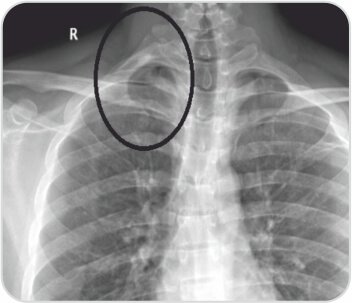

মূল্যায়নে তার ডান সম্পূর্ণ সার্ভিকাল রিব সহ ধমনী থোরাসিক আউটলেট সিন্ড্রোম পাওয়া গেছে। তাকে প্রাথমিকভাবে অ্যান্টিকোঅ্যাগুলেশন দিয়ে পরিচালিত করা হয়েছিল এবং পরে থোরাসিক আউটলেট ডিকম্প্রেশনের জন্য নেওয়া হয়েছিল। ইন্ট্রাঅপারেটিভভাবে রোগীর স্কেলিন পেশী হাইপারট্রফি এবং একটি সম্পূর্ণ জরায়ুর পাঁজর একটি বিস্তৃত প্রথম পাঁজরের সাথে মিশে গেছে যা সাবক্ল্যাভিয়ান ধমনী সংকোচন ঘটায়। ডিকম্প্রেশন পদ্ধতি অনুসরণ করে রোগীর একটি সফল ফলাফল ছিল।

জরায়ুর মুখ এবং প্রথম পাঁজর কাটা